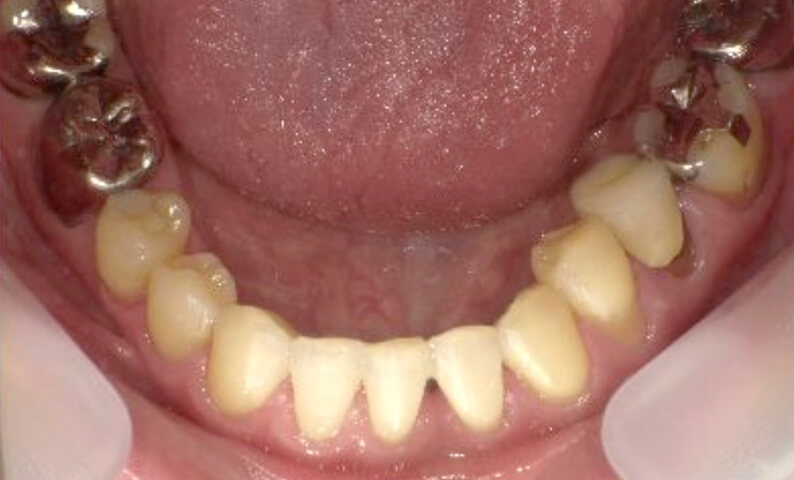

症例_003 下顎だけの部分矯正

治療期間:10ヶ月金額:24万円+税女性前歯のガタガタ下の前歯だけ上顎は補綴治療中

| Before | After |